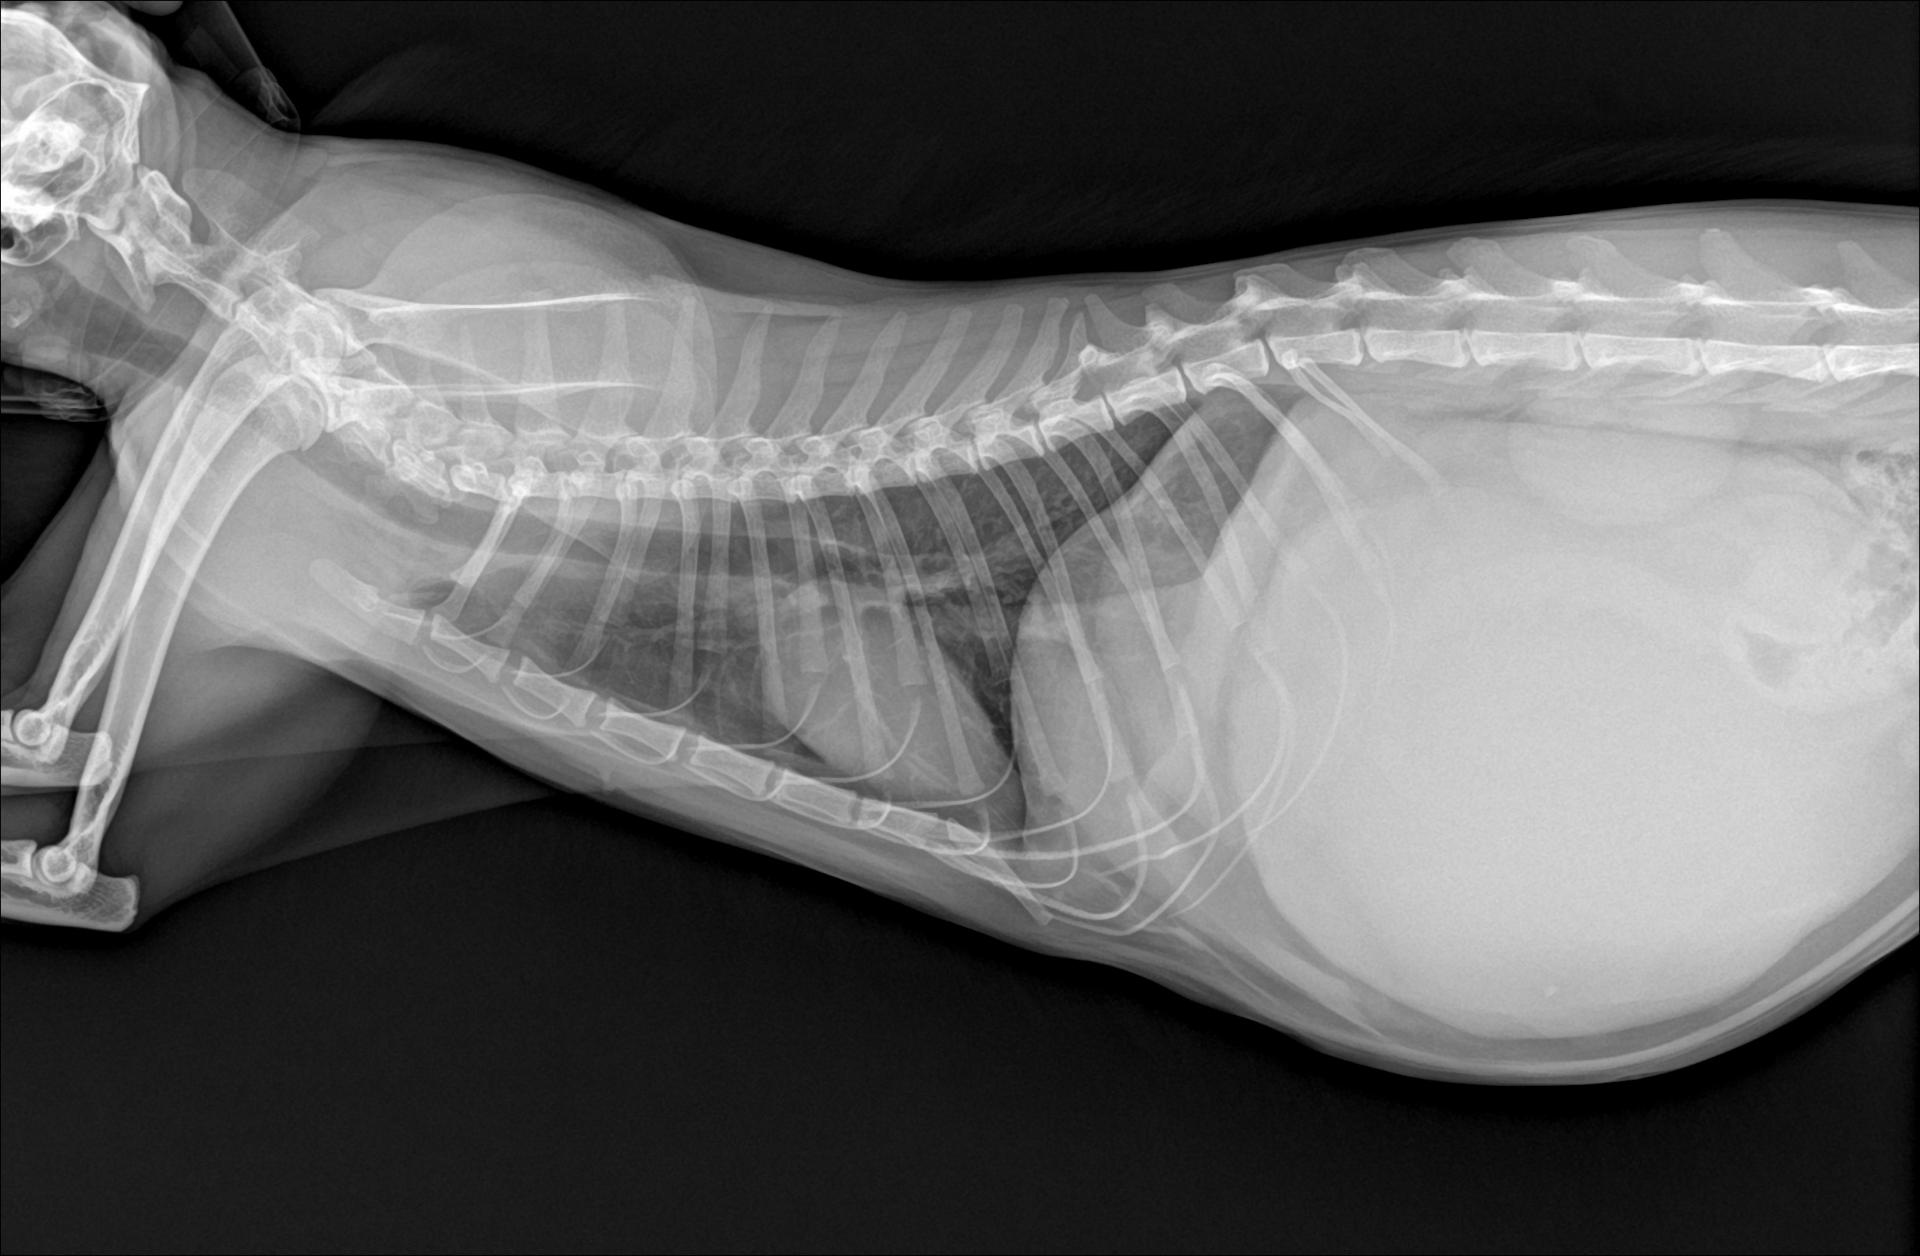

저희집 2살좀 넘은 고양이가

며칠전부터 잇몸과 귀가

창백하고 복부팽창이 심해

병원에서 x-ray를 찍었는데

선생님 말씀이 위가 비정상적으로

팽창돼 있다며 큰 병원가서

검사 받고 수술하라 하시네요

처음엔 저랑 선생님이 복막염을

의심했었는데 사진을 찍으시더니

복수같아 보이지 않으시다네요

말씀해주신 고양이의 증상인 잇몸과 귀의 창백, 복부팽창, 위 확장은 비교적 중대한 내과적 혹은 외과적 문제와 관련될 가능성이 높습니다. 창백한 점막은 빈혈, 순환장애, 또는 쇼크 전단계의 혈류 부족을 시사하며, 복부 팽창은 그 원인에 따라 크게 소화기 팽창(가스나 내용물로 인한 위 확장), 복수, 장폐색, 종양, 또는 복부 내 장기 비대 등으로 나눌 수 있습니다. 선생님께서 복수를 배제하셨다면, 현재 가장 가능성이 높은 원인은 위확장 혹은 위 확장에 의한 장폐색, 위운동 장애일 수 있습니다.

위가 비정상적으로 늘어난 경우, 위 내부에 가스나 음식물이 빠져나가지 못해 팽창하면서 주변 장기를 압박합니다. 이로 인해 혈류가 감소하고, 위벽 허혈이나 괴사, 순환장애가 동반될 수 있습니다. 특히 고양이는 개보다 위염전(GDV)이 드물지만, 장염이나 종양, 위유문부 협착, 혹은 삼킨 이물로 인해 위 내용물이 배출되지 않아 2차 확장이 생기기도 합니다. 또한 복부 팽창이 심하면 횡격막을 눌러 호흡곤란이 나타나고, 잇몸 창백이 심화될 수 있습니다. 현재 응급상황입니다.

만약 기계적 폐색이나 장 염전이 확인된다면, 빠른 외과적 처치가 예후에 결정적 영향을 미칩니다. 반대로 단순 위확장이나 위무력증(위마비)이라면 내과적 감압과 수액치료, 위장운동촉진제 투여로 호전될 수 있습니다. 빠른 진료 및 개입이 필요할 것으로 보입니다. 지체없이 이동하시길 바랍니다.